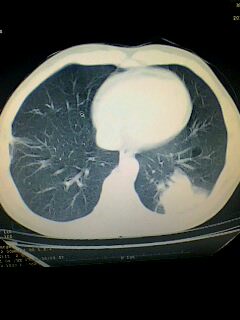

标题: CT28315:咳嗽咳痰咯血半月并胸痛 [打印本页]

标题: CT28315:咳嗽咳痰咯血半月并胸痛

1、纵膈窗效果不好,初步考虑左肺下叶感染性病灶,建议正规抗炎治疗后复查   2、右肺下叶陈旧性病灶伴局部胸膜增厚。

考虑左肺下叶周围型肺癌.图象欠清,请问病人贵更?

考虑左肺下叶周围型肺癌.

左下肺肿块影,深分叶,考虑肺癌。

左肺下叶球形肺炎,建议抗炎治疗后复查

左下肺球形病灶,考虑:1:球形肺炎;2:周围型肺癌不除外,建议治疗后复查